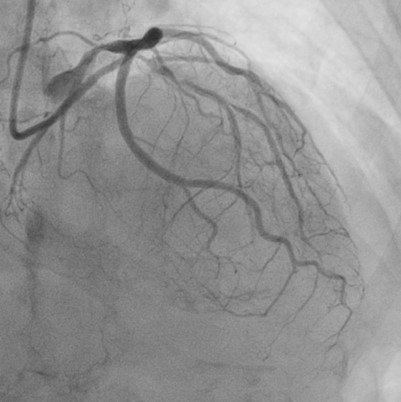

Relevant Catheterization Findings

Catheterization revealed a 95% distal left main stenosis with a calcified nodule protruding into the LAD and LCX ostia, a 99% proximal LAD lesion with an additional 90% stenosis after the first diagonal branch, non-critical LCX disease, and a 70% proximal RCA lesion with multiple critical PDA stenoses. The patient and family declined PCI in the cath lab, with a Syntax score of 40.